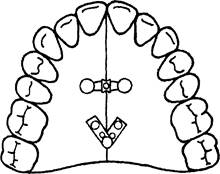

В случае вестибулярного положения клыка, причиной которого явилось мезиальное перемещение боковых зубов, можно изготовить ортодонтический аппарат для их дистального перемещения (рис. 13.40).

При двустороннем мезиальном перемещении боковой группы зубов изготавливают пластинку с двумя винтами и тремя секторальными распилами (рис. 13.41). В этом случае жевательные зубы перемещают-

Рис. 13.41. Пластинка на верхнюю челюсть с двумя винтами и тремя секторальными распилами.